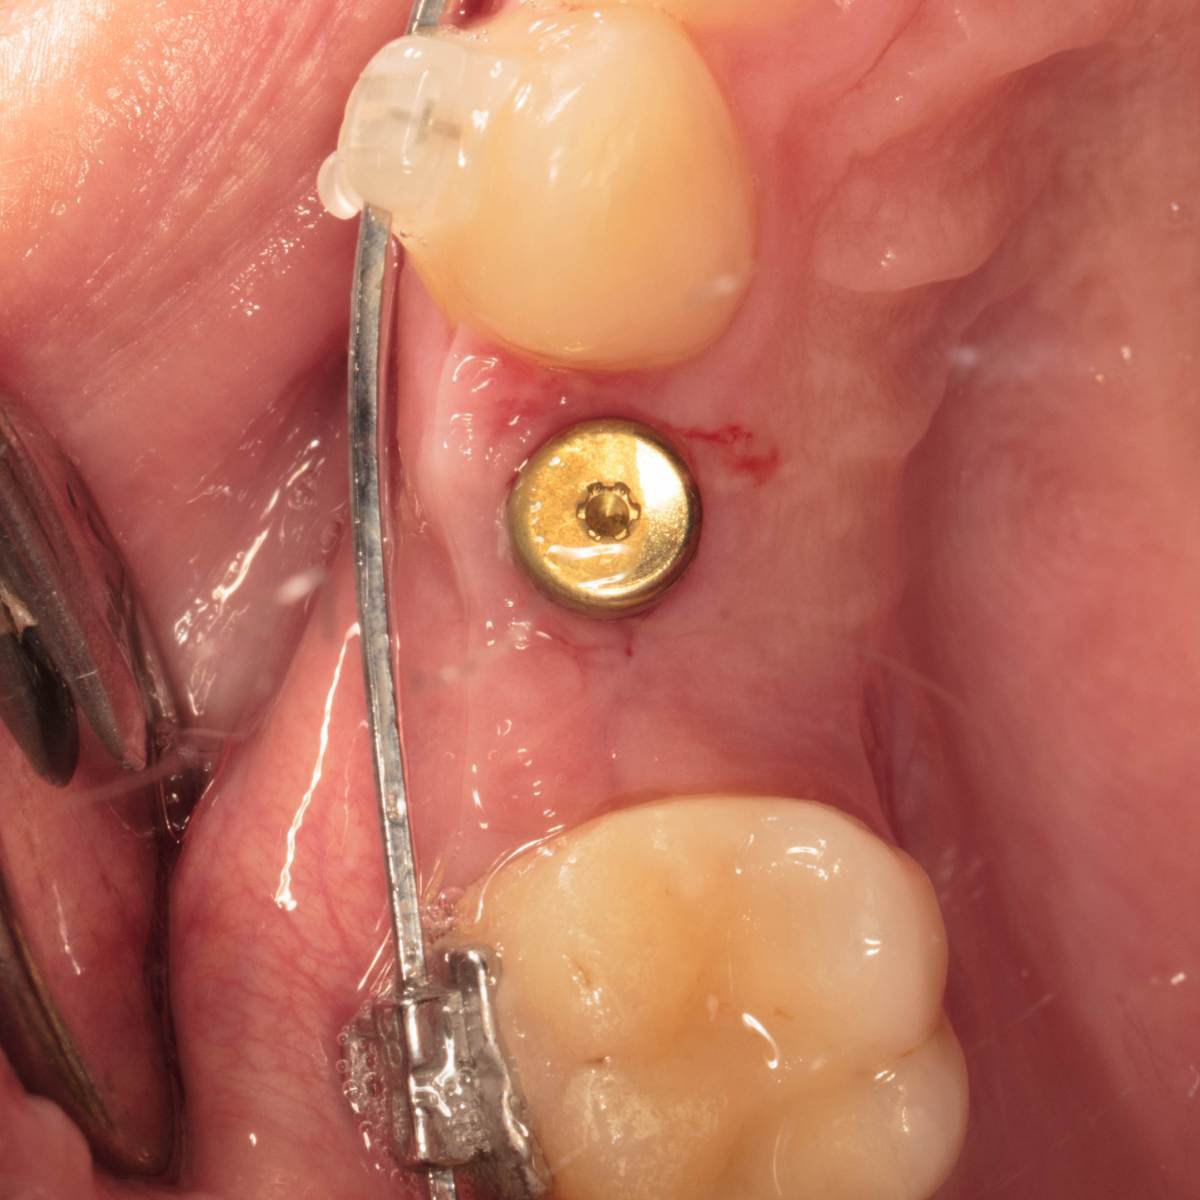

Irina xyz Опубликовано 17 ноября, 2025 Автор Поделиться Опубликовано 17 ноября, 2025 Не факт что фото информативно но это лучшее что улалось сделать Ссылка на комментарий

Irina xyz Опубликовано 17 ноября, 2025 Автор Поделиться Опубликовано 17 ноября, 2025 Это немного лучше Ссылка на комментарий

Женька Опубликовано 17 ноября, 2025 Поделиться Опубликовано 17 ноября, 2025 Пожалуй, что самое простое действительно убрать имплантат. Именно потому, что доставляет дискомфорт и боль. Хотя в полости рта я бы не сказал, что картина как-то плохо выглядит. 1 Ссылка на комментарий